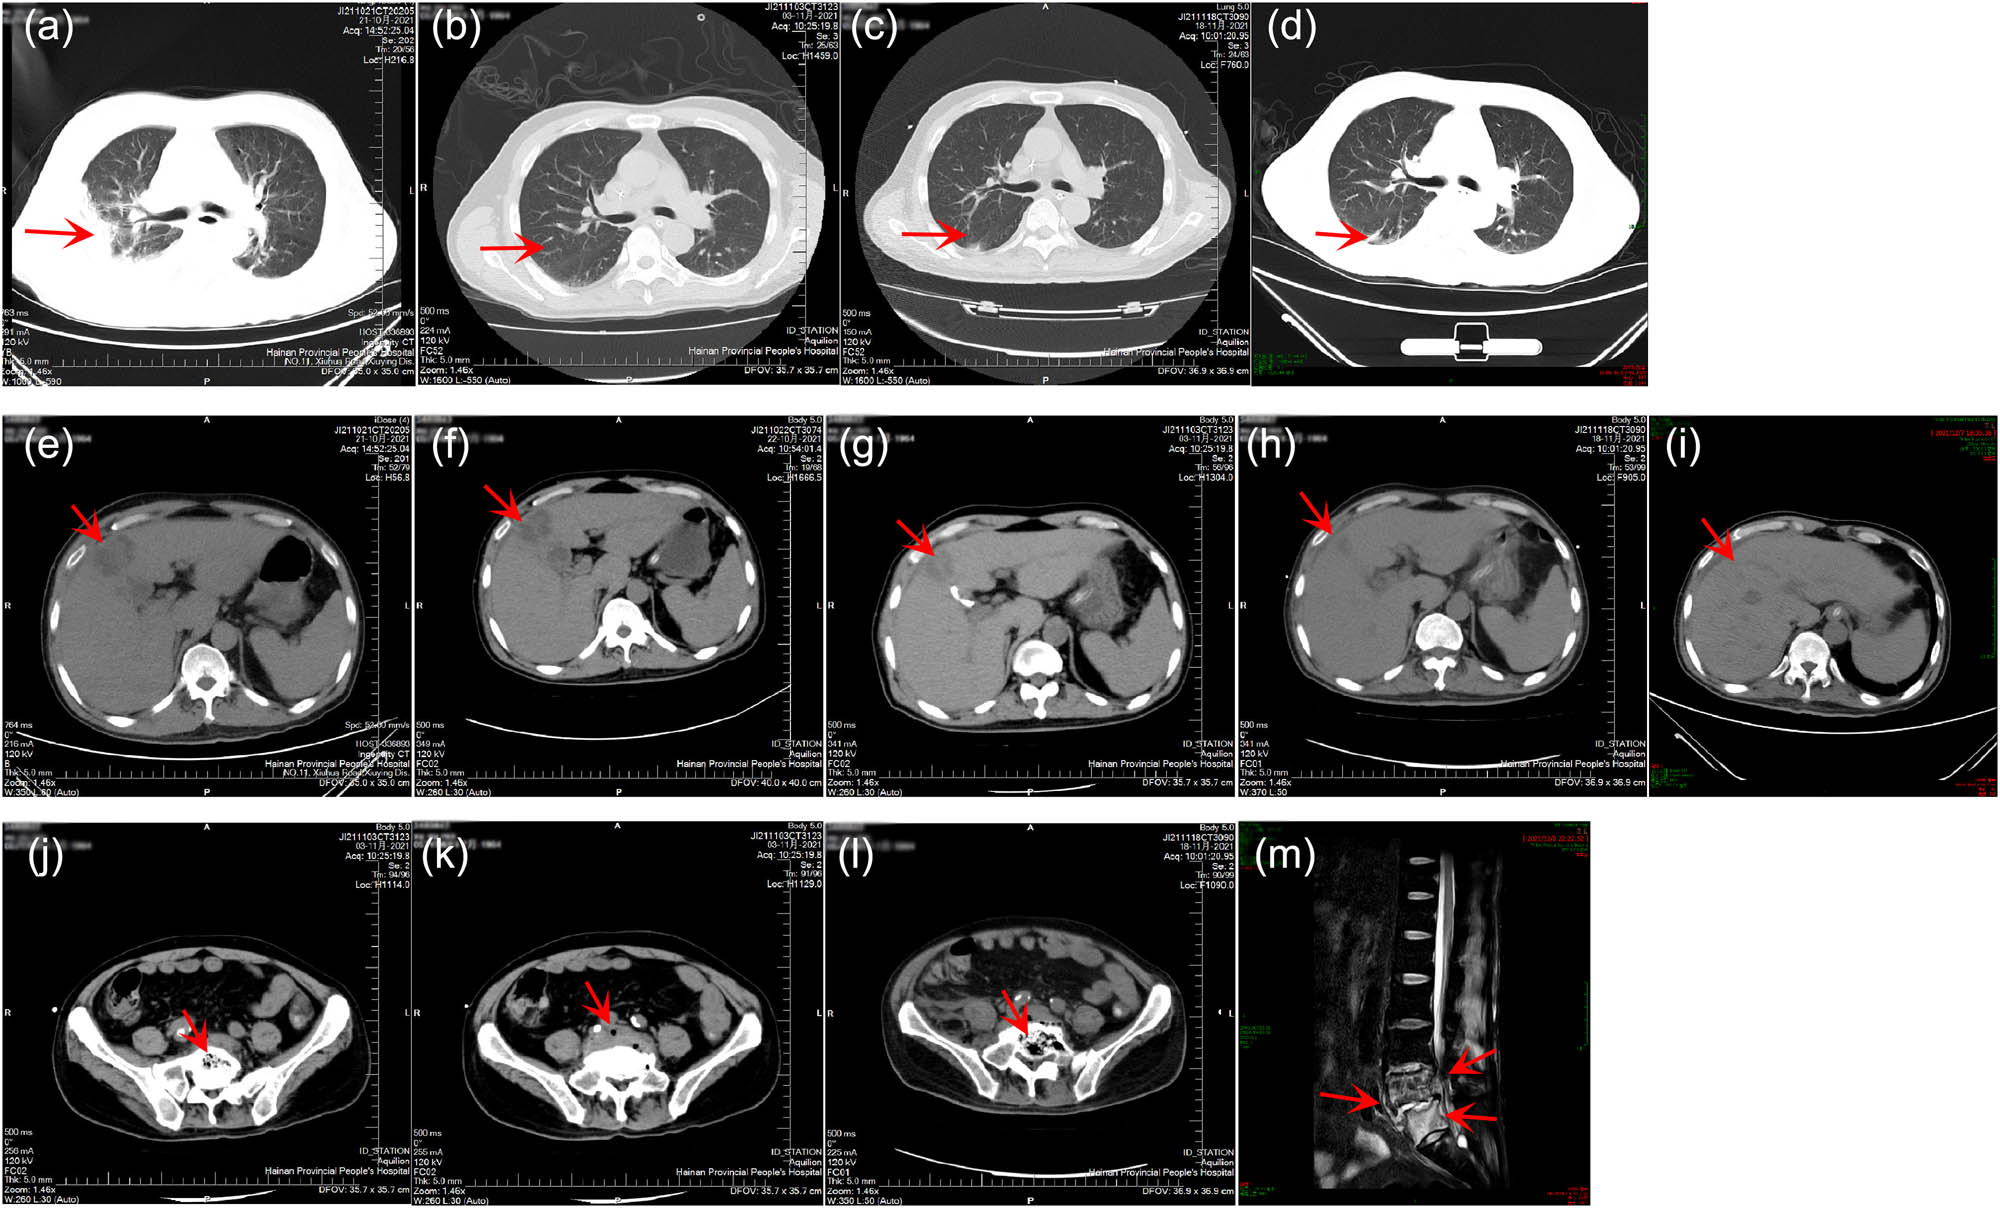

On the day of admission, his physical examination revealed a body temperature of 36.5°C, a heart rate of 72 beats per min, a respiratory rate of 27 breaths per min, a blood pressure of 110/73 mmHg, disturbance of consciousness and lethargy, coarse breathing in bilateral lungs, moist rales in the right lower lung, and abdominal distention. Blood routine showed white blood cell count (WBC) of 9.9 × 109/L (normal range, 3.5–9.5 × 109/L), decreased platelet count (PLT, 5 × 109/L; normal range, 125–350 × 109/L), and increased blood lactate (LAC, 8.91 mmol/L; normal range, 0.6–2.2 mmol/L). Infection indicator correlation analysis showed increased C-reactive protein (CRP, 312.74 mg/L; normal range, 0–6 mg/L) and procalcitonin (PCT, 100.0 ng/mL; normal range, <0.046 ng/mL). Liver function indicator analysis showed direct bilirubin (D-Bil) of 139.43 μmol/L (normal range, 0–8 μmol/L), indirect bilirubin (I-Bil) of 74.66 μmol/L (normal range, 0–26 μmol/L), and blood creatinine (Scr) of 341 μmol/L (normal range, 57–111 μmol/L). Computed tomography (CT) showed high-density shadows and exudation in the right lung, and quasi-circular low-density lesions with unclear borders in the liver (Figure 2a and e). Suspected vertebral endplate cartilage inflammation was considered but the cause of degeneration could not be ruled out.

Imaging test results of the patient. (a)–(d) Lung CT results on October 21 (Day 1), November 3 (Day 14), November 18 (Day 29), and December 7 (Day 48), respectively. (e)–(i) Liver CT results on October 21 (Day 1), October 22 (Day 2), November 3 (Day 14), November 18 (Day 29), and December 7 (Day 48), respectively. (j) and (k) Abdominal CT results on November 3 (Day 14). (l) Abdominal CT results on November 18 (Day 29). (m) Lumbar MRI results on December 8 (Day 49).

Enhanced CT on October 22 (Day 2) revealed quasi-circular low-density lesions (2.5 cm × 3.8 cm), indicating liver abscess (Figure 2f). Percutaneous abscess drainage was performed. Culture using blood (Days 1 and 2) and liver abscess drainage fluid (Day 2) was performed, indicating K. pneumoniae. A drug susceptibility test was performed and showed no resistance (Table 1). The blood sample (Day 3) was simultaneously collected for mNGS detection, which revealed a total of 19,013 unique reads of K. pneumoniae with a genome coverage of 27.51% (Figure 3a). The patient was initially diagnosed with a liver abscess complicated with bloodstream infection and pulmonary infection caused by K. pneumoniae. Imipenem combined with cilastatin sodium (both 0.5 g q6h) was given for anti-infective treatment, accompanied by continuous renal replacement therapy and puncture drainage for liver abscess. On November 3 (Day 14), repeated CT showed that the liver abscess was slightly smaller (2.4 cm × 3.0 cm), and suspicious foci of infection in the L5 vertebral body and paravertebral soft tissues were found (Figure 2b, g, and j). Considering the positive K. pneumoniae in blood and liver abscess drainage fluid, as well as the subsequent infection in multiple tissues, hvKp was suspected, which has been reported to be more likely to cause liver abscesses with extrahepatic complications [2]. WGS (Hugobiotech, Beijing, China) was therefore performed using the preserved strains from the culture of blood and liver abscess drainage fluid. High homology (99.999%) between the two strains was identified, indicating hematogenous dissemination. Multiple virulence genes were also detected in the two strains, including five important aerobactin-related virulence genes, 17 colibactin-related virulence genes, two LPS-related virulence genes, one rmpA-related virulence gene, four Sal-related virulence genes, and 11 Ybt-related virulence genes. The specific plasmid could not be determined due to the incomplete assembly of plasmid sequences. Multilocus sequence typing showed a novel genotype of this isolate. Accordingly, the patient was finally diagnosed with a liver abscess complicated with multiple organ-invasive infection caused by hematogenous disseminated hvKp. Repeated mNGS using blood and liver abscess drainage fluid on November 4 (Day 15) revealed 2,336 and 729,151 unique reads of K. pneumoniae (Figure 3b and c), respectively. Though the number of unique reads of K. pneumoniae in blood decreased, it remained high in liver abscess drainage fluid. The shortness of breath of the patient was relieved but he still had a fever. The antibiotic treatment continued.

On November 9 (Day 20), repeated blood routine showed WBC of 19.14 × 109/L, PLT of 259 × 109/L, CRP of 202.32 mg/L, and PCT of 2.91 ng/mL. The conditions of the patient improved, and the antibiotic was switched to moxifloxacin 0.4 g qd. The patient was transferred to the general ward on November 12 (Day 23). However, his condition deteriorated with a body temperature of 39.5°C, a WBC of 12.25 × 109/L, a PLT of 319 × 109/L, a CRP of 60.05 mg/L, and a PCT of 0.621 ng/mL, and serum creatinine of 141 μmol/L. Tigecycline 50 mg was added for anti-infective treatment. The body temperature was still high, and lethargy occurred. K. pneumoniae was still positive by repeated blood culture (Day 27). On November 17 (Day 28), the patient was transferred to the ICU again. Moxifloxacin was switched to meropenem (1.0 g q8h). The condition of the patient improved. The temperature dropped to 37.8°C on November 18 (Day 29). Repeated CT showed that the liver abscess was significantly smaller (2.2 cm × 2.0 cm), but suspicious infectious lesions in the paravertebral soft tissues were unchanged, exudative lesions in the lower lobes of bilateral lungs, around the right psoas muscle, and in the right pelvic wall even developed (Figure 2c, h, and k). The dosage of meropenem was optimized to 0.5 g q3h on November 19 (Day 30).

On November 23 (Day 34), surgical drainage treatment was performed on this patient due to significant swelling of the soft tissue of the right lower limb. The patient’s body temperature dropped to normal on November 24 (Day 35) and the condition gradually improved. Repeated CT before discharge (Day 48) showed infectious lesions of vertebral endplate cartilage and multiple scattered exudations or inflammation of para-vertebral soft tissues, waist muscle, and hip muscle (Figure 2d and i). The patient still suffered exudative lesions in the lower lobes of bilateral lungs but the pleural effusion was basically absorbed. His liver abscess was relieved compared to before but low-density lesions were still observed (Figure 2l and m). After 6 months of follow-up, the patient recovered, with difficulty in walking but no other discomforts.